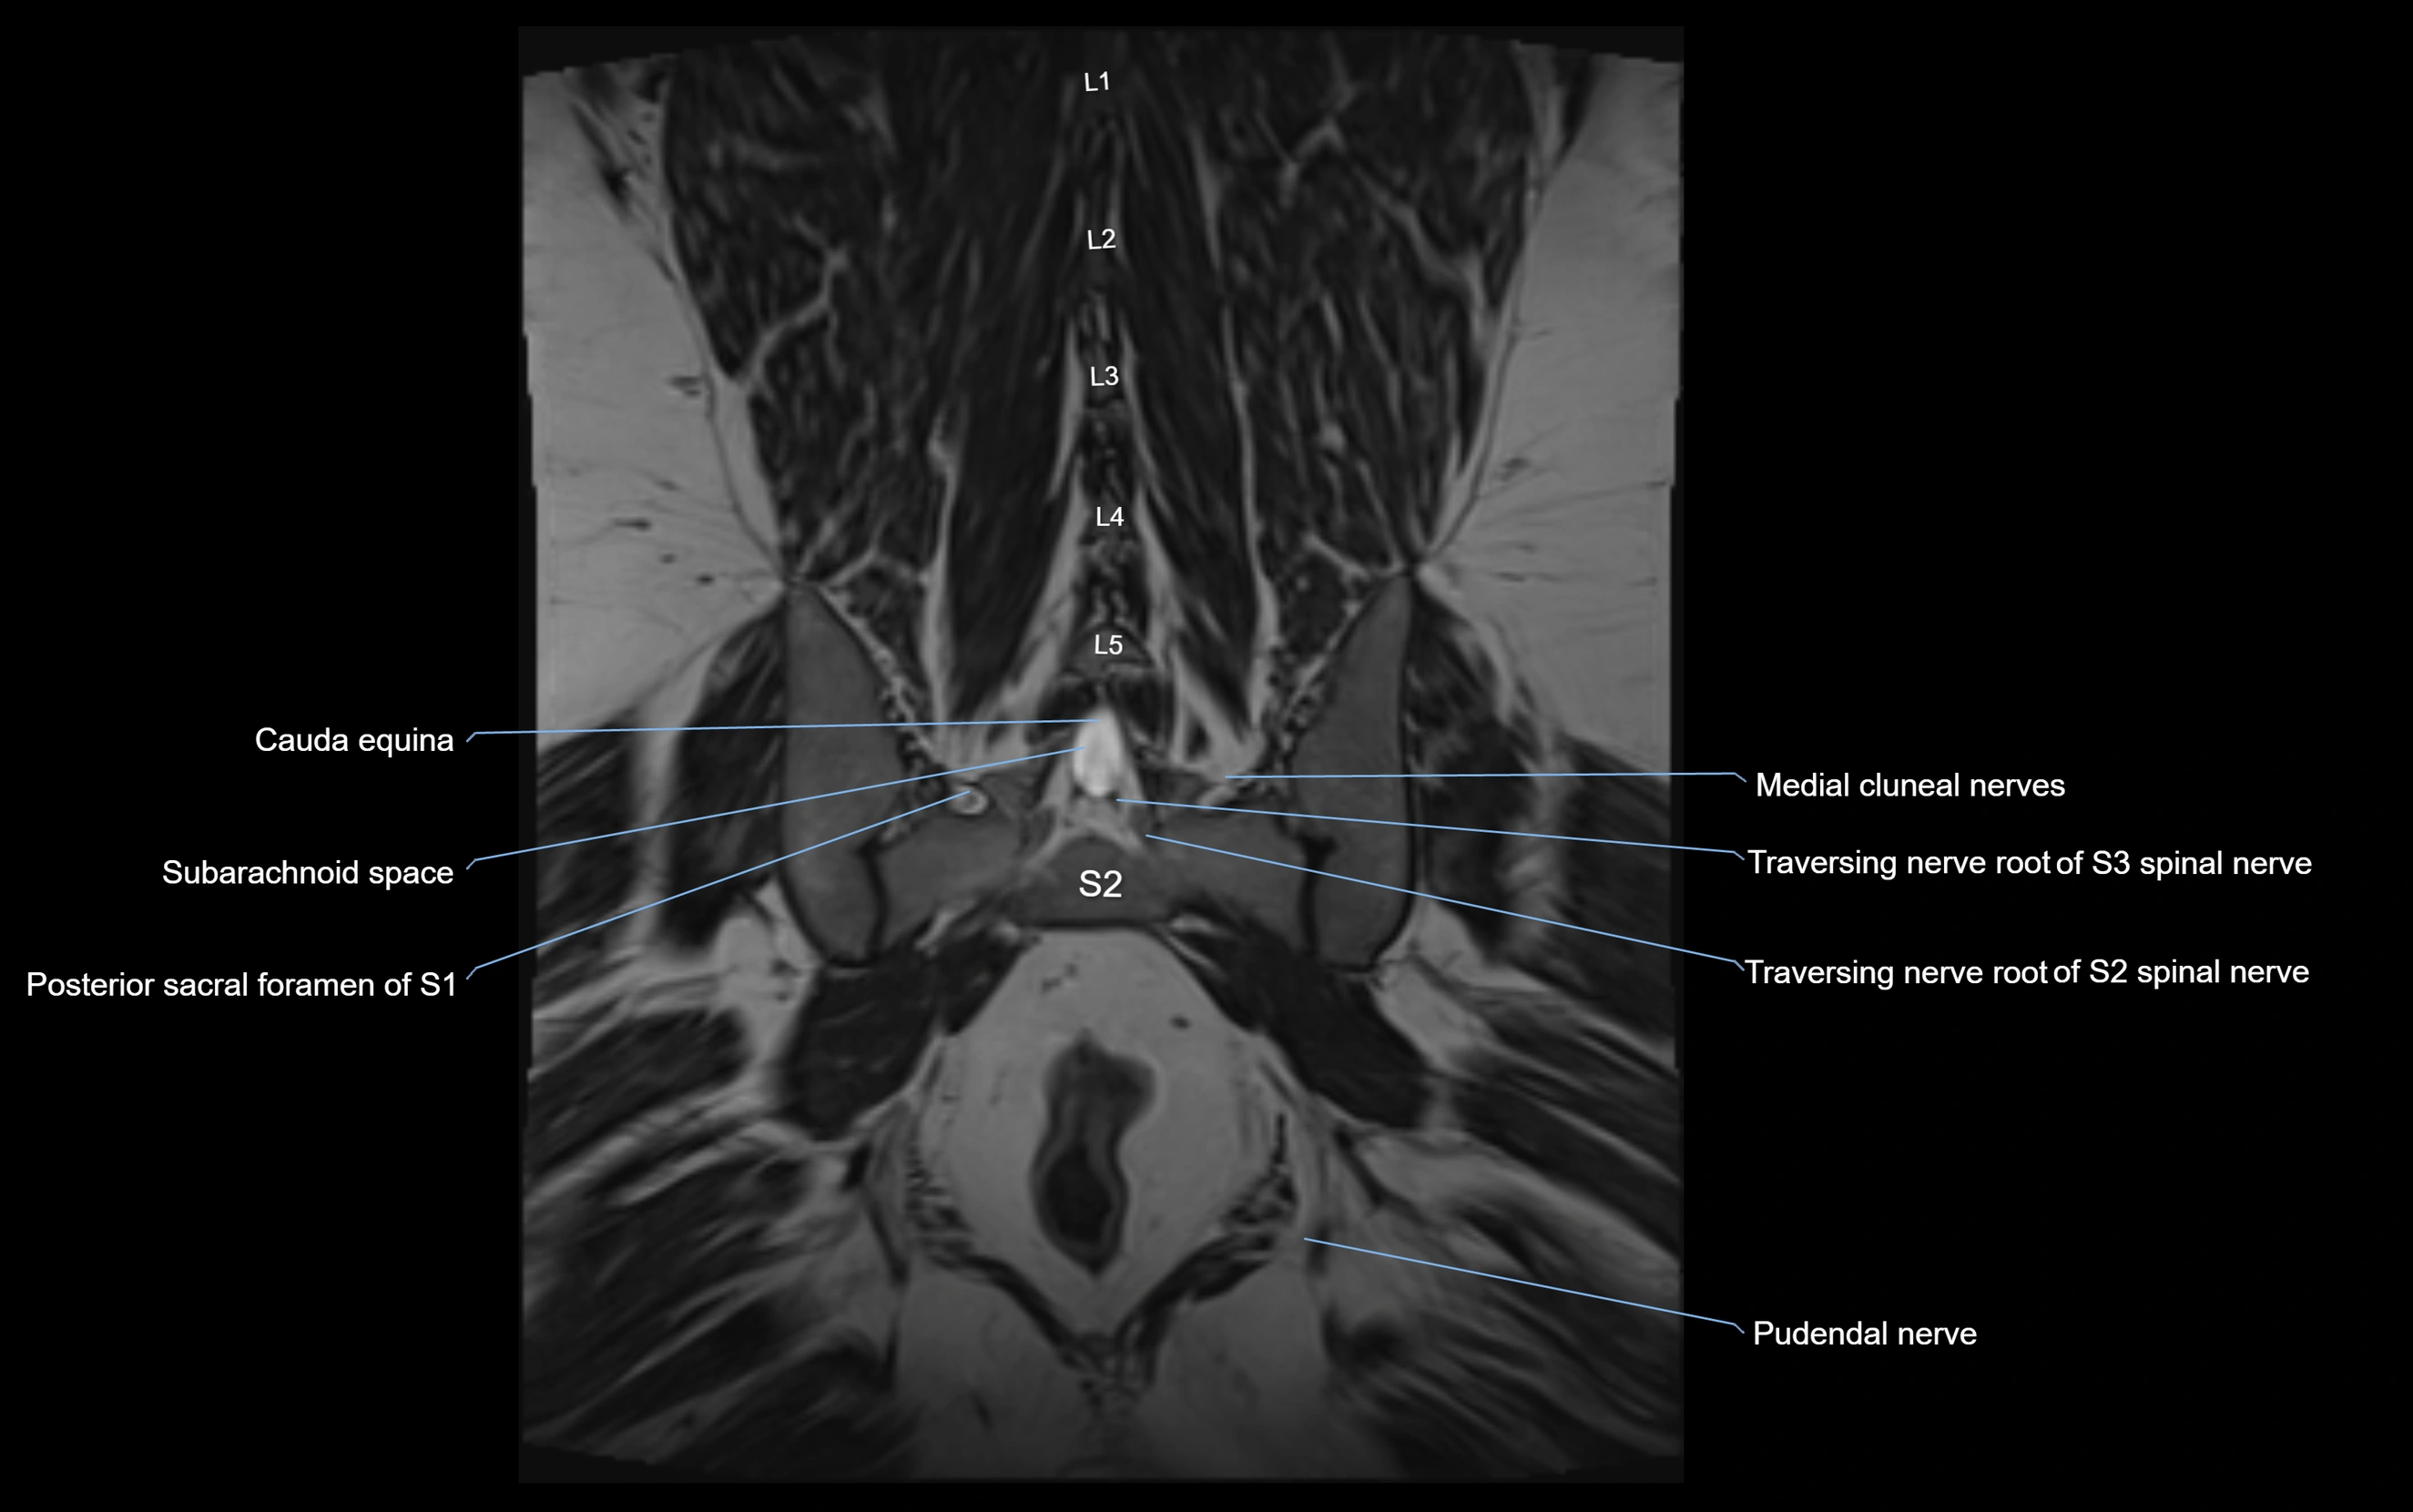

MRI image

image